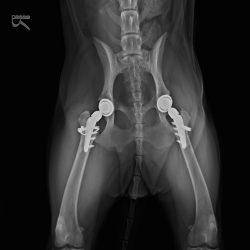

骨折や脱臼、前十字靭帯断裂、関節疾患など、犬や猫の「動くこと」に関わるさまざまなトラブルに対応しています。

CTなどの画像診断を活用し、原因を正確に見極めたうえで、外科手術からリハビリまで一貫した治療を行います。

当院では、骨折や靭帯損傷などの高度な整形外科手術を数多く行っていますが、術後のリハビリなしに円滑な回復や本来の運動機能の再獲得はあり得ません。